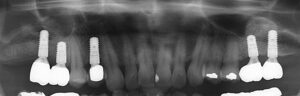

初診時

初診時